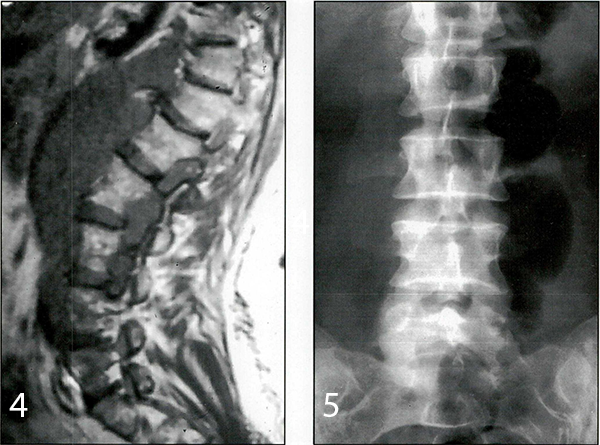

Caso 3: paciente de sexo femenino y 23 años de edad, con antecedentes de haber sido operada en su infancia de un tumor neurogénico abdominal, concurrió a la consulta con IRM que mostraban un tejido blando hiperintenso con respecto al LCR entre D12 y L4, ubicado en el espacio pre y paravertebral retroperitoneal, que se introducía dentro del canal espinal a través de los forámenes (Figs. 3 y 4). La paciente estaba asintomática. La oncóloga solicitó una biopsia para conocer la patología y luego poder indicar el tratamiento definitivo.

Fig. 3. IRM axial ponderarla en T1 que muestra un tejido blando hiperintenso con respecto al LCR ubicado a nivel extra e intraforaminal que invade el canal espinal.

Fig .4. IRM sagital pondera d a enT 1 que muestra un tejido blando hiperintenso con respecto al LCR ubicado extensamente a nivel prevertebral e intraforaminal.